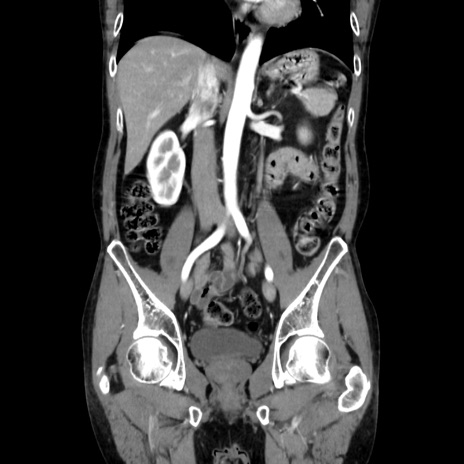

症例37(冠状断像)

【症例】40歳代 男性

【主訴】腹痛

【現病歴】4時間ほど前に電車に乗車中に臍部上より腹痛出現。徐々に増悪し起立困難となり、救急外来受診。生ものは数日食べていない。今朝お雑煮を食べた。

【身体所見】BT 36.8℃、BP 117/84mmHg、HR 91/min、SpO2 97%、苦悶様、腹部:臍上部広範囲圧痛あり、反跳痛±

【データ】WBC 8100、CRP 0.03